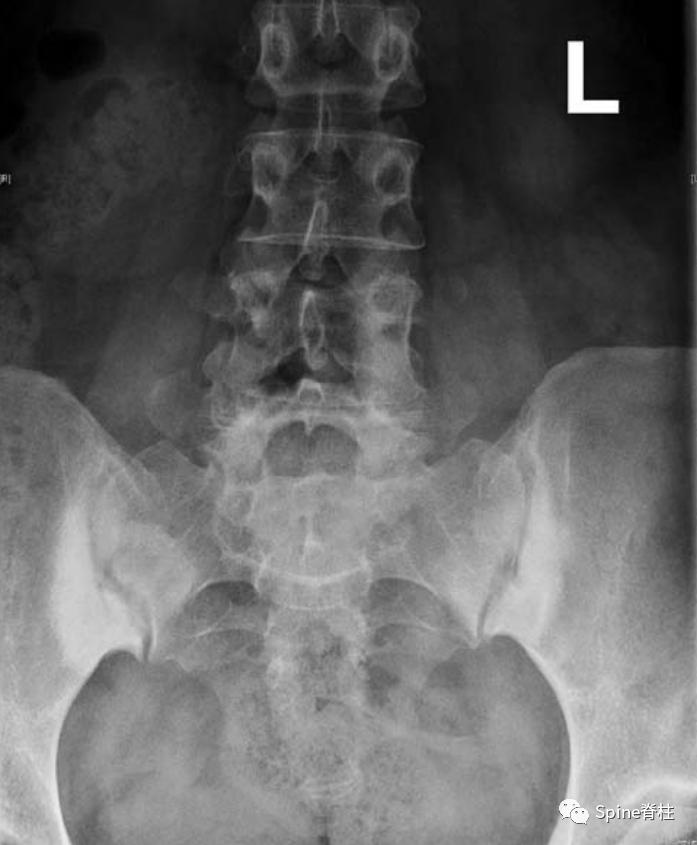

髂骨致密性骨炎通常是偶然诊断出来的。骶髂关节的髂侧表现出硬化,通常呈双侧、对称和三角形。硬化区轮廓分明且致密,主要位于关节的前中三分之一处。诊断主要依靠影像学上无骶骨受累和关节间隙变窄,但可能会出现骶骨附近对称性小局灶性硬化。此外,单侧髂骨致密性骨炎已有文献报道。

骶髂关节的双侧硬化,主要累及关节的髂骨部分。注: 特征明确的三角硬化Rheumatol Int (2010) 30:293–29